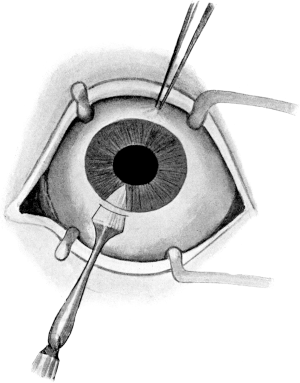

| 94. | Lens Extraction | 196 |

| 134. | Enucleation | 257 |